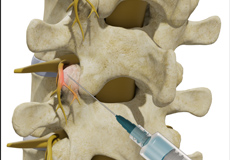

Epidural Spinal Injection

Epidural spinal injection is a non-surgical treatment option utilized for relieving back pain. Spine degenerative conditions such as herniated disc, spinal stenosis and many others may induce back pain due to the compression of the associated spinal nerves. This pain or numbness may extend to the other parts of the body such as hips, buttocks, and legs. Doctors start with non-surgical methods to treat back pain and epidural spinal injection is one of these preferences. In cases where the patient finds no relief from non-surgical methods then finally surgery is recommended.

Epidural Steroid Injections

Epidural steroid injection (ESI) is a minimally invasive approach to treat inflammation of spinal nerves that causes pain in the neck, arms, back and legs. This technique may help relieve back pain in conditions such as spinal stenosis, spondylolysis or herniated discs. In this technique, the steroidal medications are injected into the spinal canal so as to pass down to the inflamed spinal nerve through the epidural space which lies between the covering of the spinal cord and the vertebrae. An ESI contains a corticosteroid medication along with an anesthetic agent which can reduce the inflammation and pain.